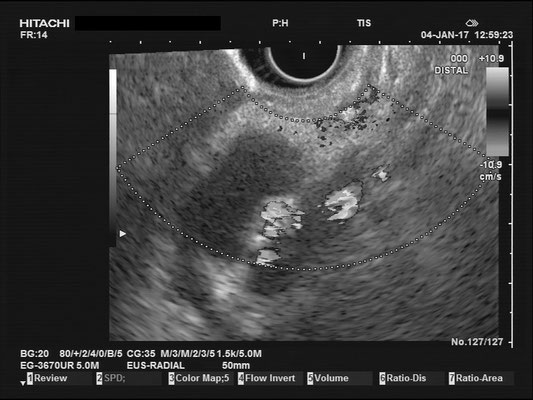

The images above depict a thorough inspection of the pancreas, as seen in an radial EUS Examination. We begin (hopefully ;) bei identifying the uncinate process between the golden V, which is formed by the aorta/V. cava and the mesenteric vessels. After spotting die usually hypoechoic ventral pancreatic root, the duodenal papilla can be identified (for a more detailed approach, please visit "Learning Endosono"). By following the splenic vein, the body and tail of the pancreas can be examined.

The most observant viewers will have noticed that not all images above depict normal findings but some abnormalities. (my bad ;)